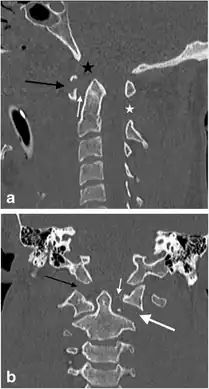

a,b)Jefferson’s fracture in a male victim of a motor vehicle accident -

Axial CT scan showing a Jefferson fracture.